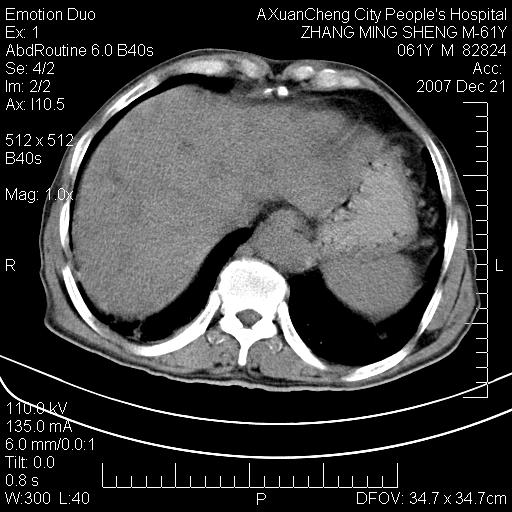

标题: CT11031:M61Y,胰腺占位 [打印本页]

标题: CT11031:M61Y,胰腺占位

大家侃侃门静脉和胆管系统怎么回事,肝内转移?

胰腺癌肝转移

肝硬化,门脉高压,脾肿大;弥漫性肝癌,肝内、门脉、腹膜后淋巴结转移,肝内外胆管扩张,胰头区占位,建议mr检查

胰腺癌伴肝内转移;门脉、肠系膜上v癌栓形成。

考虑为:胰腺癌伴肝脏转移、腹膜后淋巴结转移,门静脉及肠系膜上静脉瘤栓形成。

胰体尾癌伴肝内转移,门静脉及肠系膜上静脉瘤栓形成.

肝硬化,脾大. 胰腺癌伴肝内转移;门脉、肠系膜上v癌栓形成。